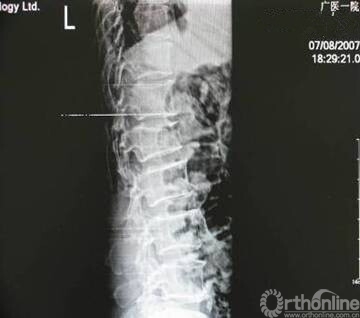

本学科脊柱外科诊断、治疗水平高,技术全面,与国际发展同步。很多复杂和高难度技术、新技术都是国内最先或较早开展;对脊柱侧弯的发展演变研究、矫形手术治疗,切除脊柱肿瘤,后路椎间盘镜的应用,经皮椎弓根螺钉固定手术,内窥镜脊柱手术等达到国际水平。

经皮椎弓根螺钉固定术、微切口椎管减压固定术、内窥镜脊柱手术、穿刺射频消融、术中放疗术、颈椎微创融合固定术等的应用和创新,标志着骨科研究所微创脊柱外科技术水平与国际同步,特别是经皮螺钉固定术水平达到国际先进水平,率先应用横突探触法及多点进钉法,使手术时间明显缩短,X线曝光率减少一半以上;在国际上最先对长臂螺钉经皮植入进行研究和改造并取得突破,该项技术应用规模省内领先。